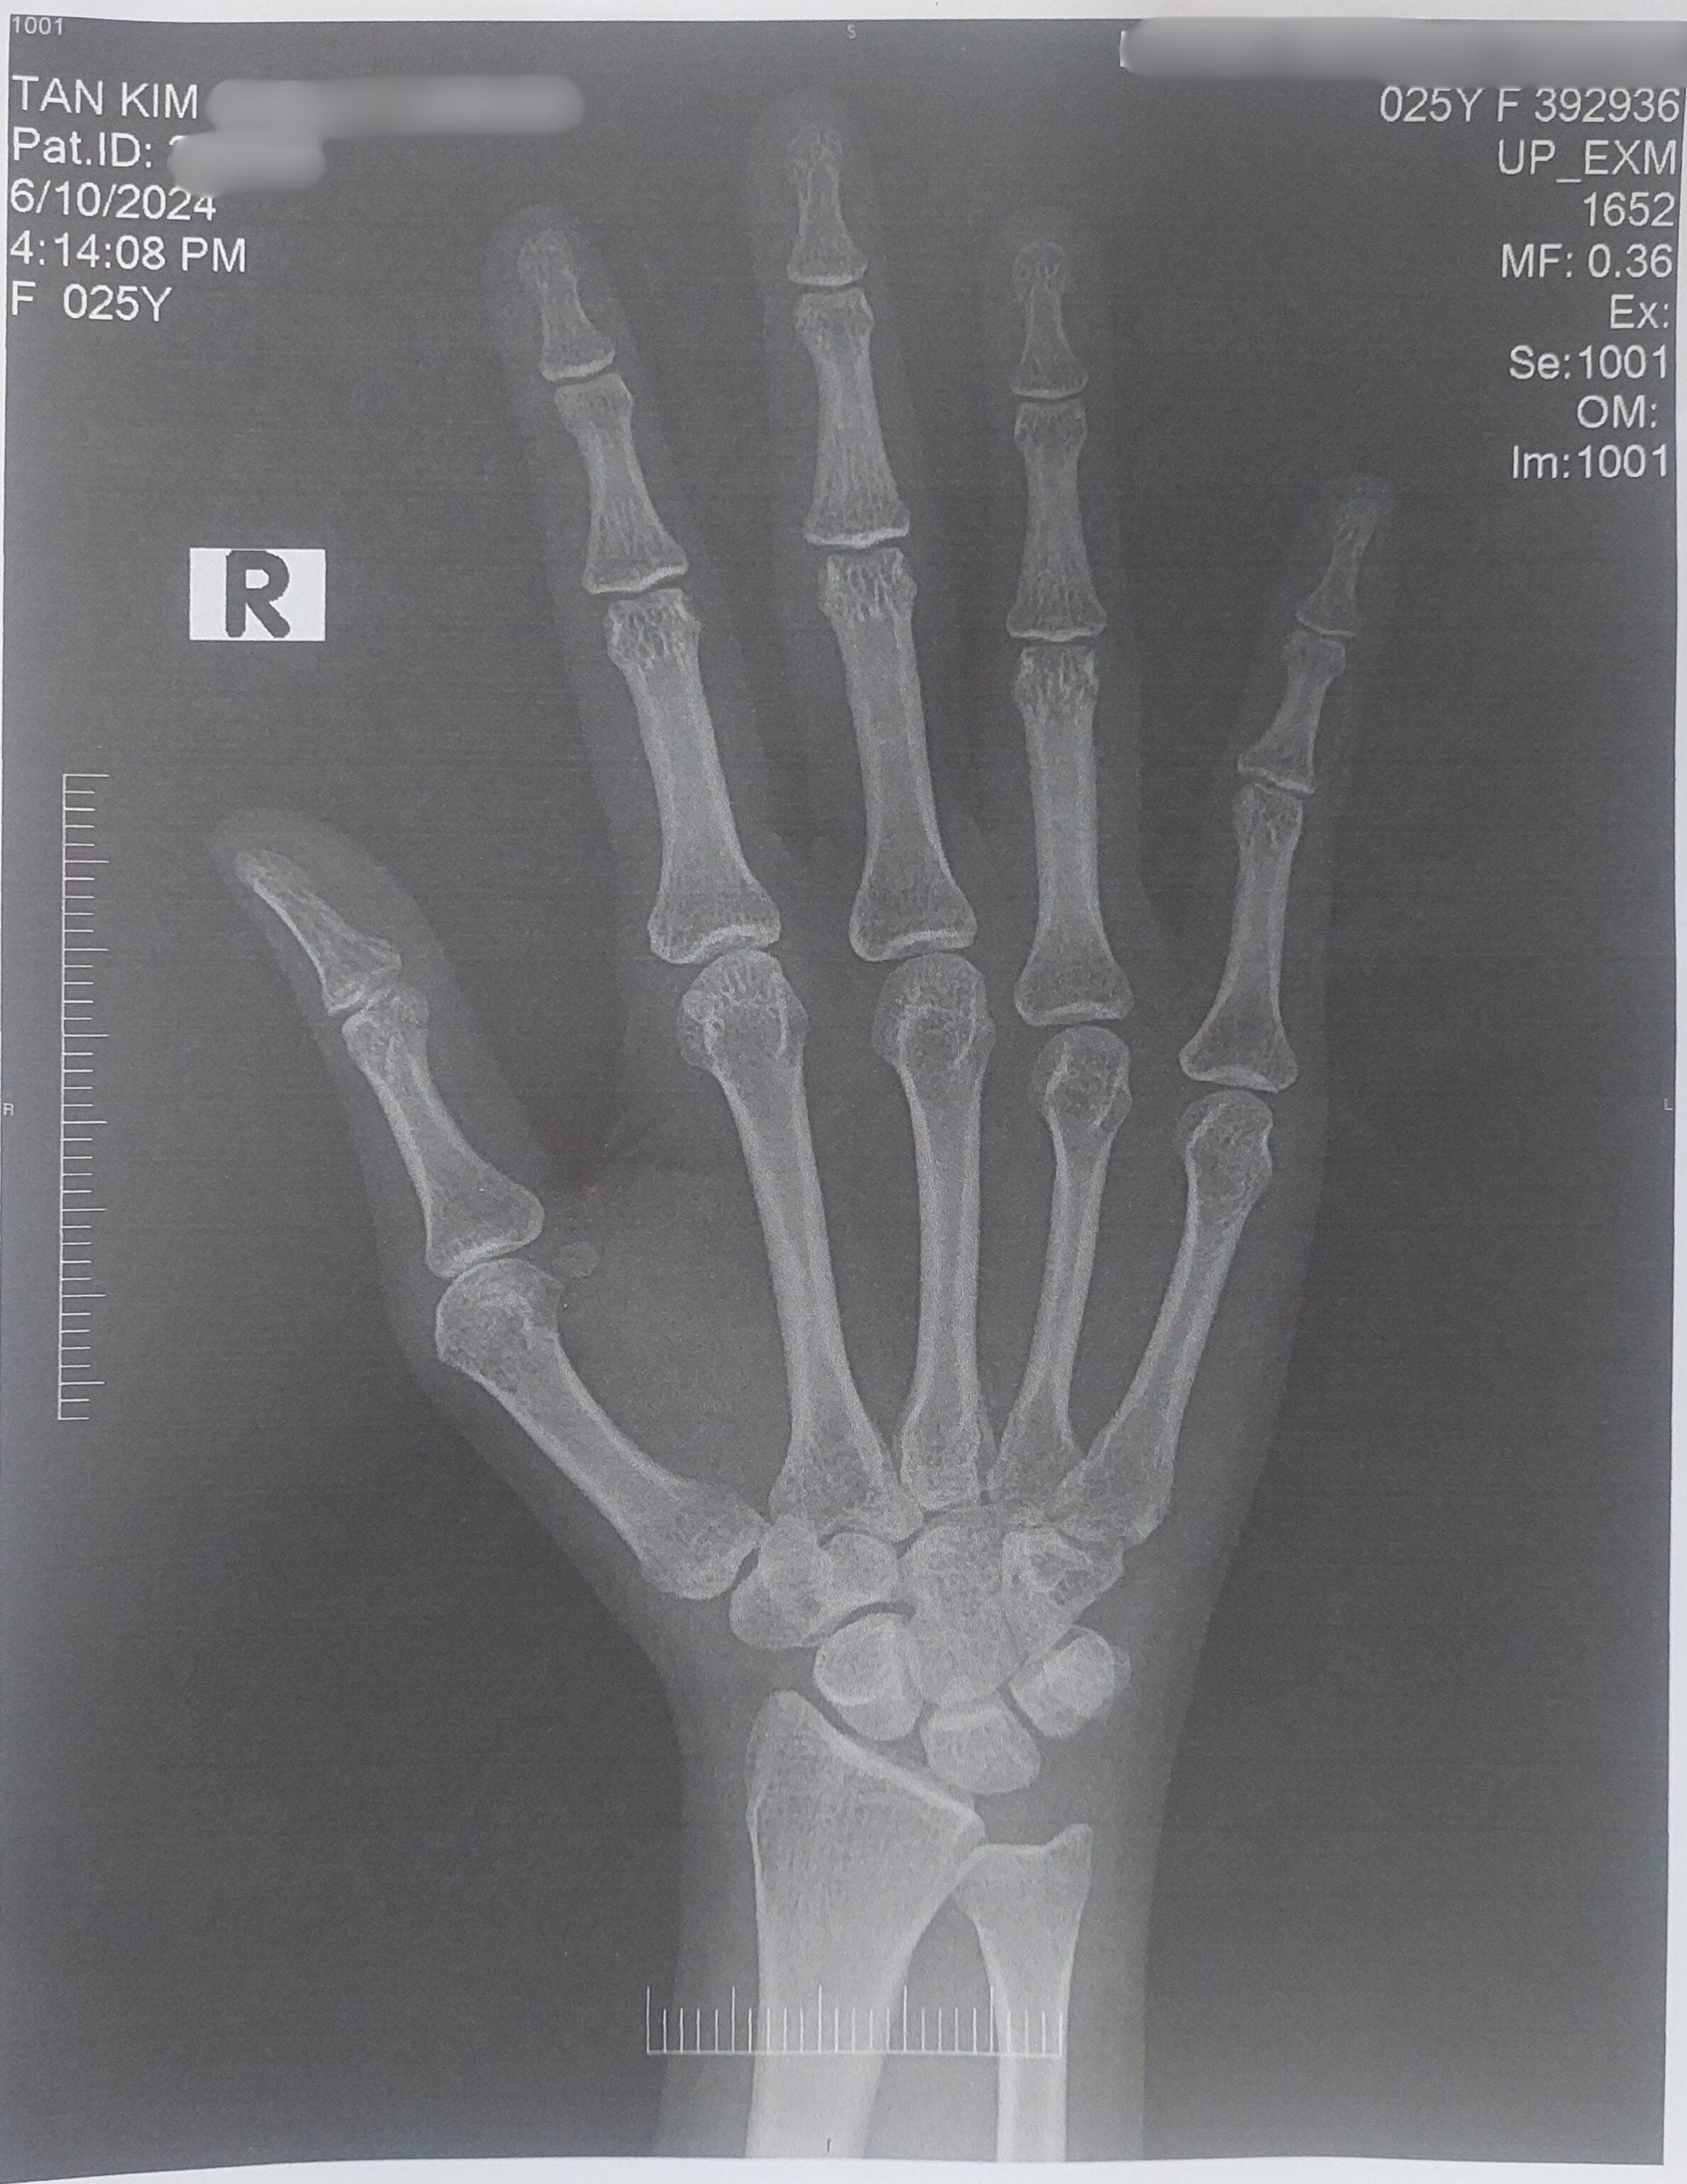

An X-ray and a blood test later, he confirmed I had arthritis at age 25.

If left untreated, it can cause irreparable damage to my joints and put me at risk of developing heart conditions.